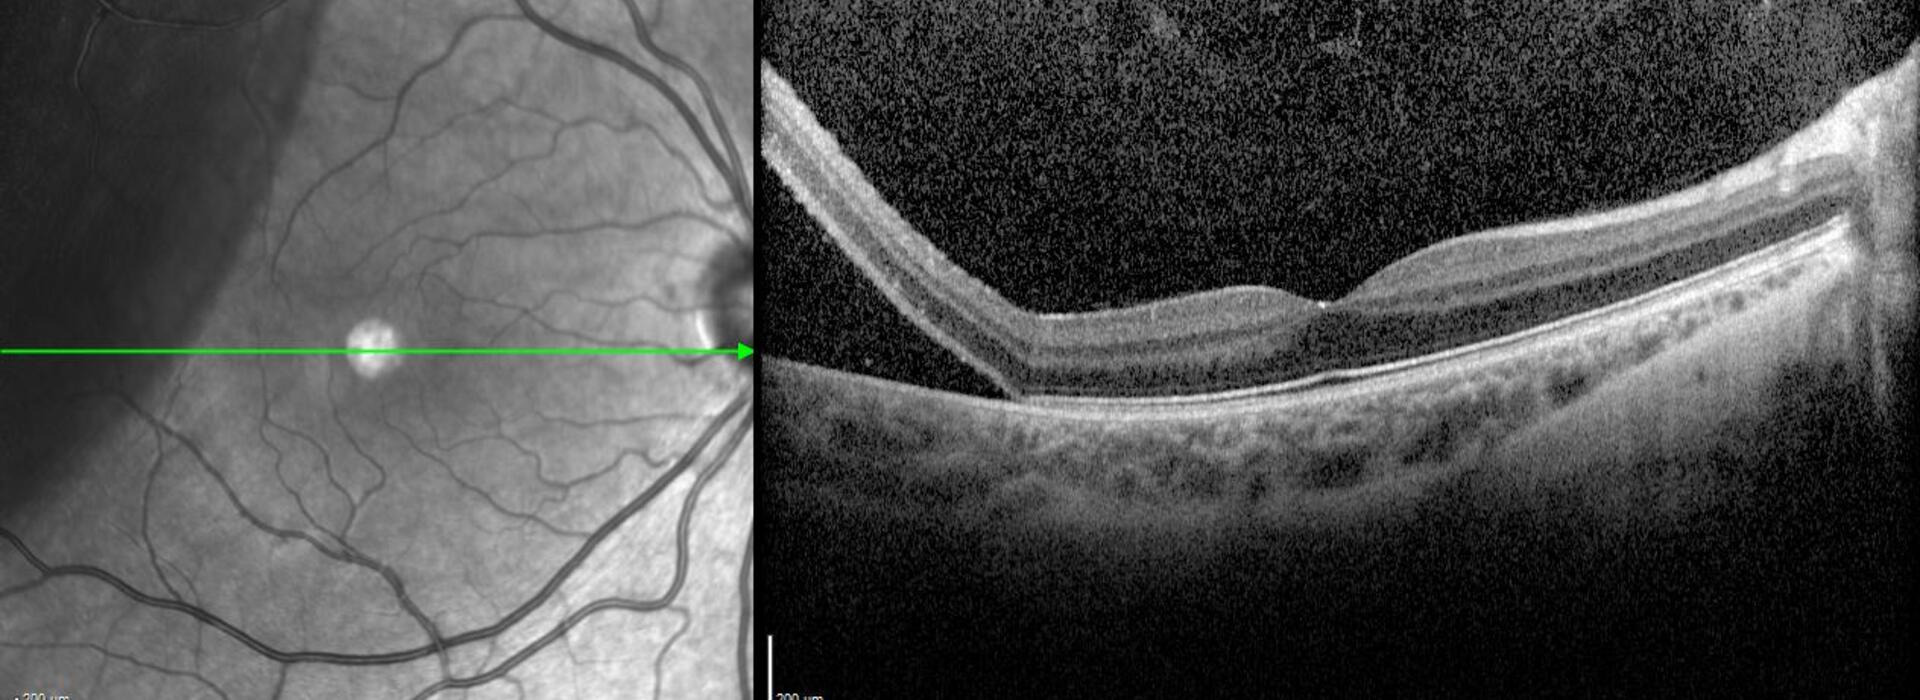

El Dr. Juan Manuel Cubero realiza una revisión práctica de los sistemas actuales de OCT intraoperatoria, describiendo sus principales características y evidencias. Expone sus aplicaciones más útiles en cirugía vitreorretiniana —MER, STVM, DR, PVR, retinopatía diabética proliferativa, miopía y cirugía pediátrica— destacando su impacto en la toma de decisiones intraoperatorias.

Actualización en OCT intraoperatoria